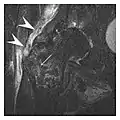

Figure 13: Partial osseous avulsion of the gluteal muscles at the greater trochanter in a 59-year-old man who presented with the right hip pain without a history of trauma. Lauenstein view and anteroposterior and radiographs (not shown) did not show an obvious fracture line or disruption of bony contours in the acetabulum or the right femoral neck. (a) Coronal T1-weighted MRI displays an incomplete fracture line extending partially from the greater trochanter (arrow). (b) Coronal short tau inversion recovery MRI shows heterogeneous hyperintensity in the same region (arrow) as well as hyperintensity within the gluteus medius and minimus muscles (arrowheads) consistent with tissue edema and hematoma.[1]